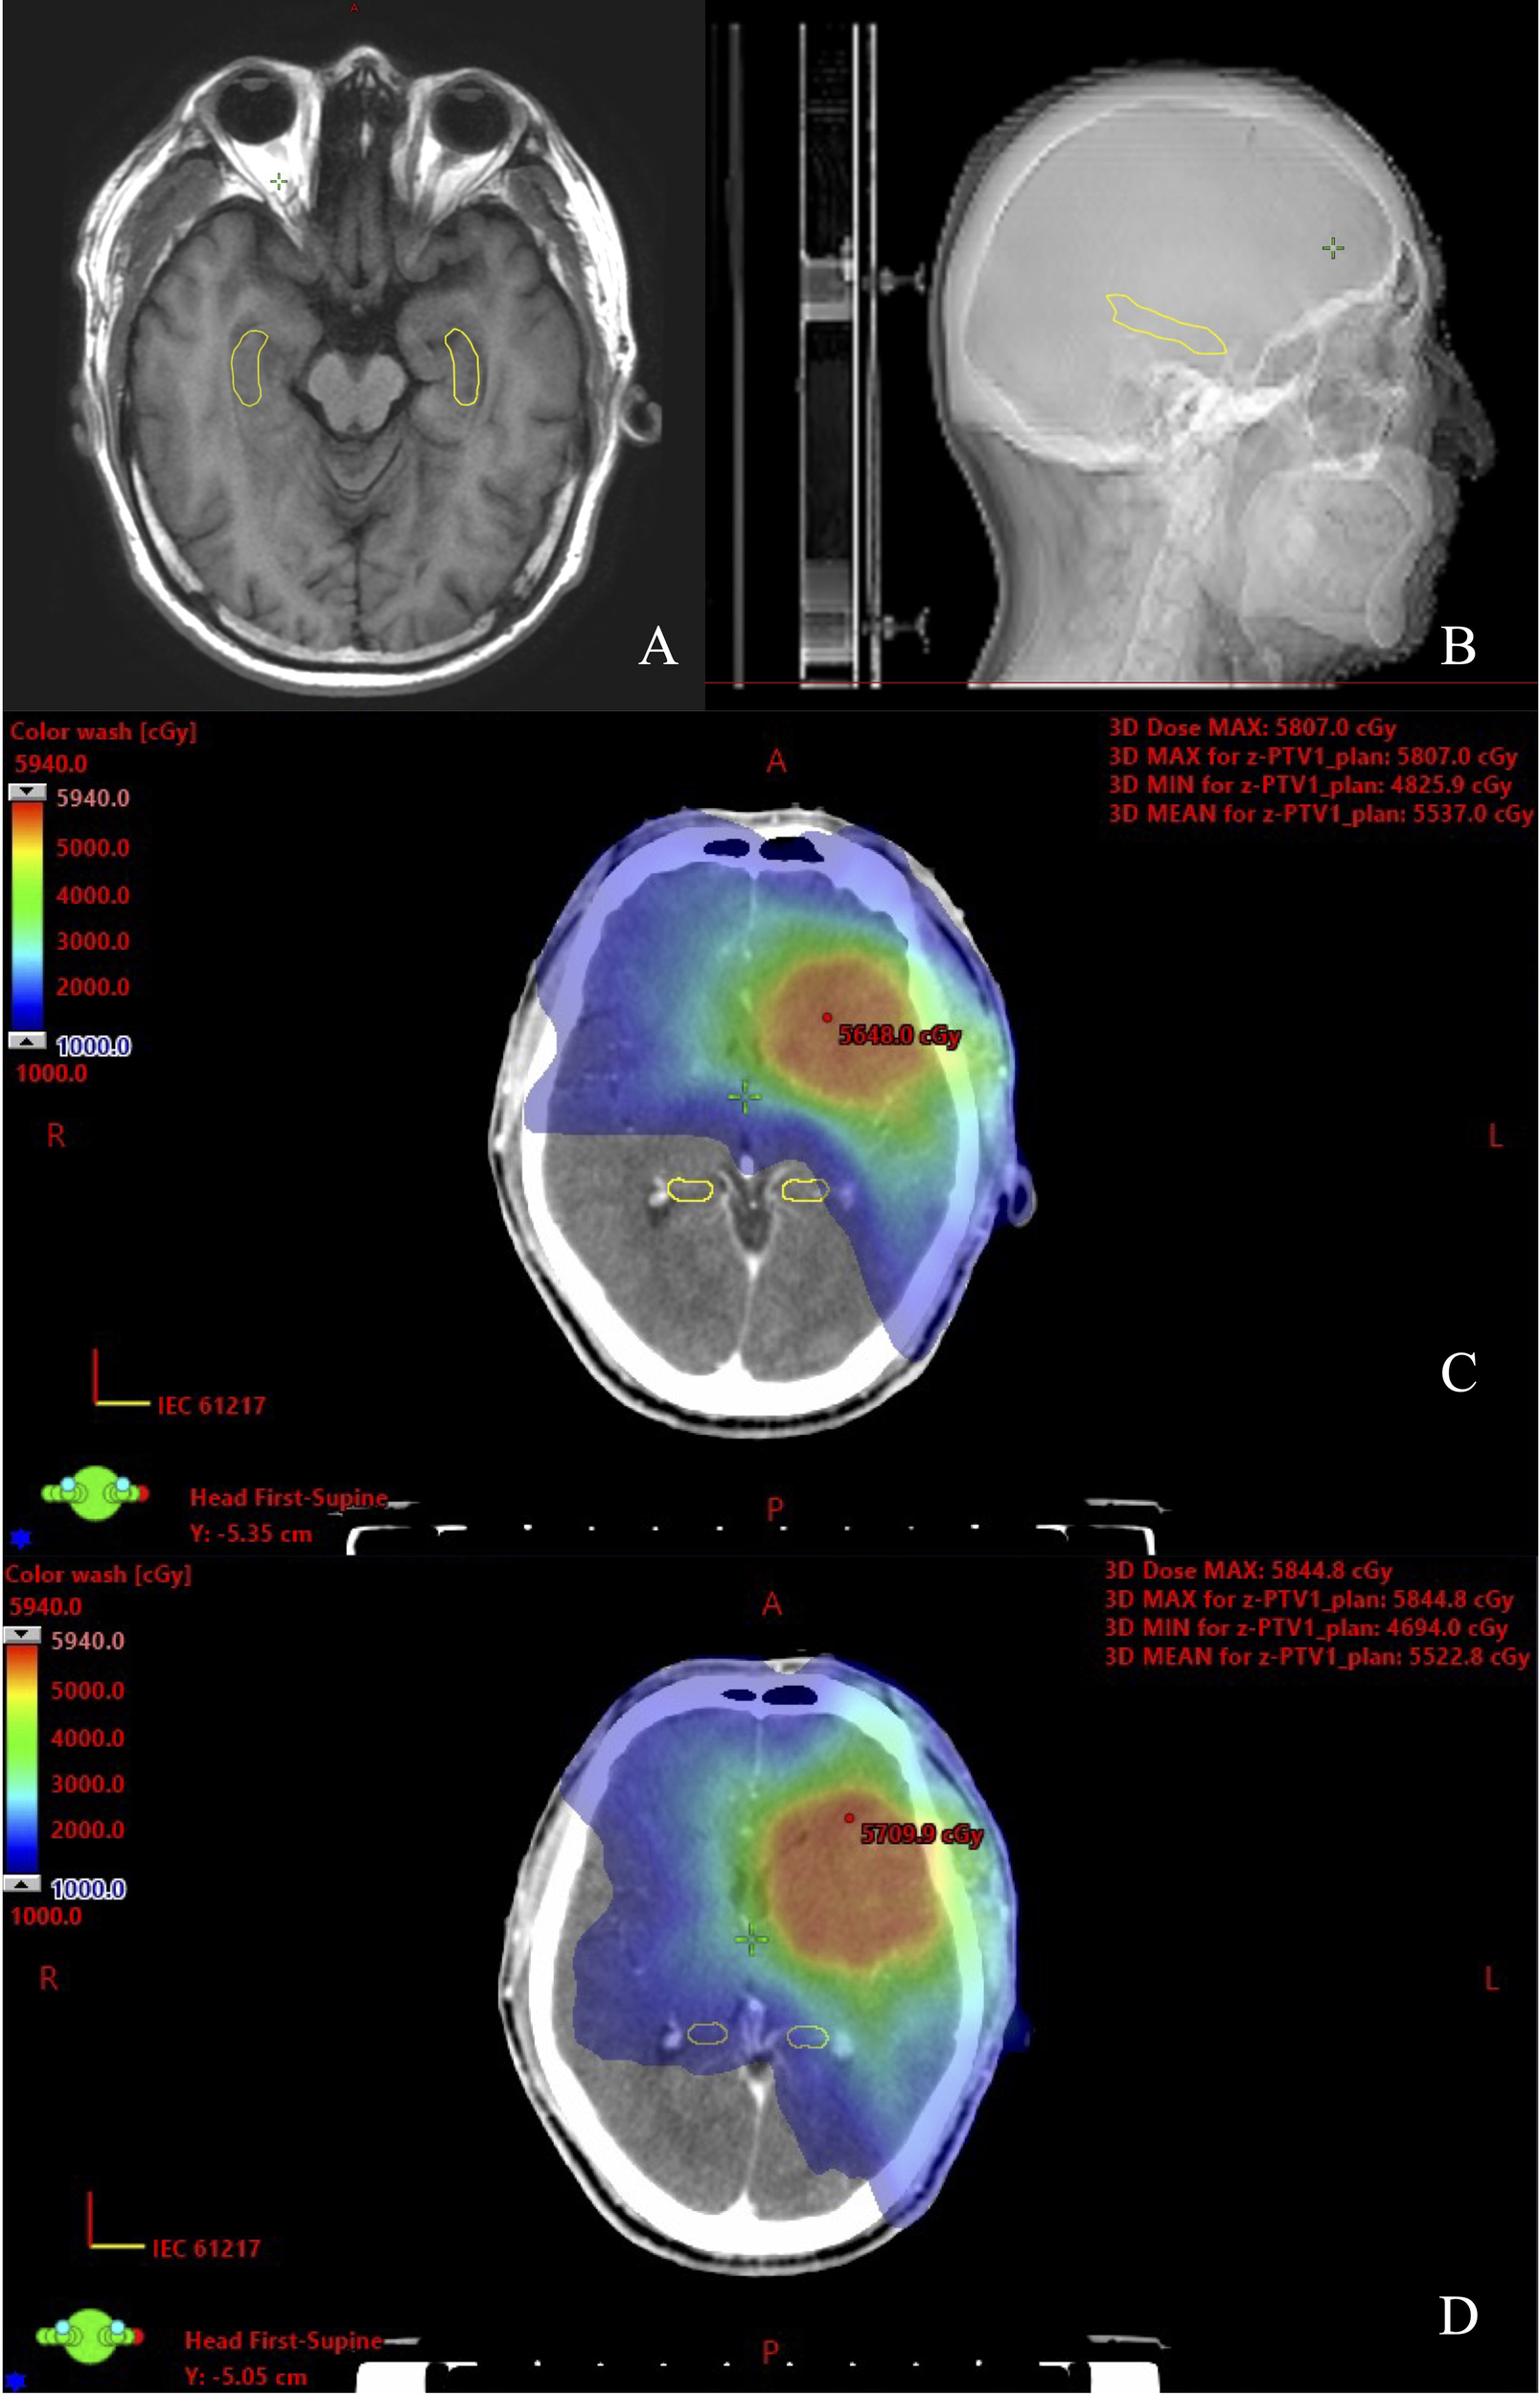

All of the HS VMAT plans and NHS VMAT plans were clinically acceptable. The dose distributions for the NHS VMAT plans and HS VMAT plans in one patient are shown in Figure 1. Table 2 displays the simulated radiation dose for the PTVminus in both plans. The CI and HI analyses were analyzed utilizing the paired-sample t-test. The HI (0.057 ± 0.014 vs. 0.046 ± 0.009, p=0.011*) and CI (0.91 ± 0.02 vs. 0.92 ± 0.02, p=0.071) of HS VMAT plans had no significant differences compared with NHS VMAT plans. The DVH of the PTV54 in one glioma case for NHS VMAT plans and HS VMAT plans is shown in Figure 2. The above results indicated that the HS VMAT plans were not inferior to the traditional NHS VMAT plans in terms of dose distribution.

Figure 1

www.frontiersin.org

Figure 1. View of dose distribution of the hippocampus contoured on CT-MRI fusion for one glioma case. (A) Hippocampal contour in transverse plane. (B) Hippocampal contour in sagittal plane. (C) HS VMAT plans. (D) NHS VMAT plans.